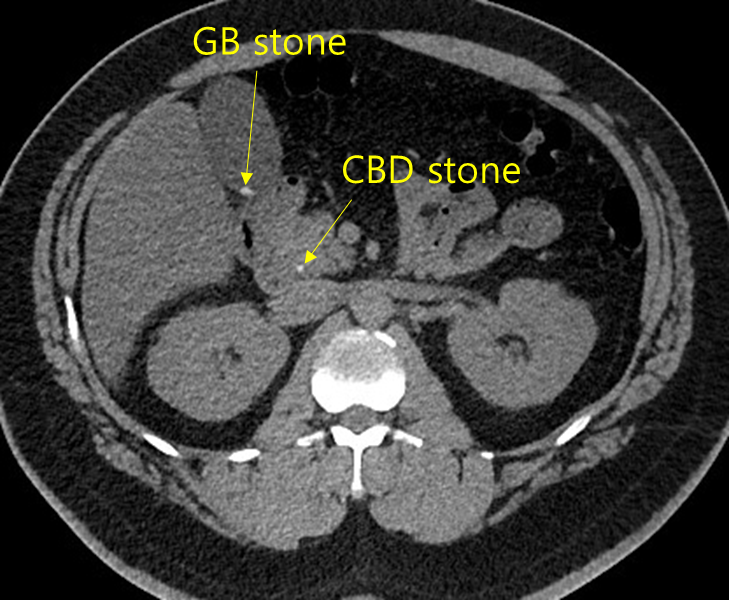

Img | CT: GB stone, CBD stone, inflammation around CBD |

발열, 담즙정체, CT상 CBD 주위 염증 및 CBD/GB stone이 확인되므로 급성 담관염 진단 하, ERCP를 통한 stone removal을 시행한다.

• 급성 담관염 진단을 위해 시행한 non-contrast CT상 GB 내부에 stone 1개, CBD에 stone 1개가 확인되며 CBD 주위에 지저분한 염증이 있으므로 급성 담관염으로 진단한다.